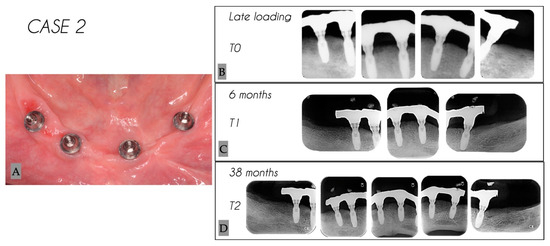

| 2 | Male | 63 | Mandible | 4 |

| Case No. | Tooth No. | Initial MBL (mm) | MBL 6 Months (mm) | MBL 38 Months (mm) | KM 6 Months (mm) | KM 38 Months (mm) |

|---|---|---|---|---|---|---|

| 2 | 34 | 0 | 1.25 | 1.40 | 2 | 2 |

| 2 | 32 | 0 | 1.44 | 1.51 | 3 | 3 |

| 2 | 42 | 0 | 1.74 | 1.79 | 1 | 1 |

| 2 | 44 | 0 | 1.86 | 1.94 | 2 | 2 |

| Mean | 0 | 1.57 | 1.66 | 2.0 | 2.0 | |